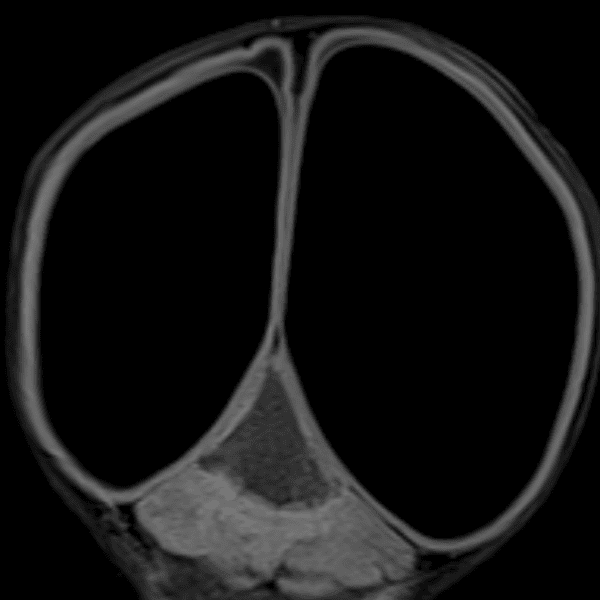

Classic Cases